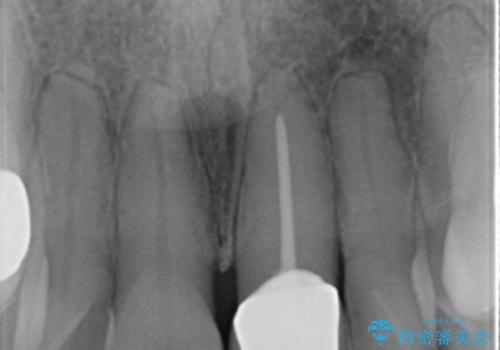

生まれつき小さな歯を矮小歯と言います。

矮小歯は、歯列の中で空隙の原因となったり審美的な問題を引き起こすことがあります。

今回、特に病的な状態とは言えませんが審美面の改善を希望されたので最小限歯を削合しオールセラミックジルコニアクラウンで審美性の改善を行いました。

同時に行った根管治療でも良好な結果が見られています。